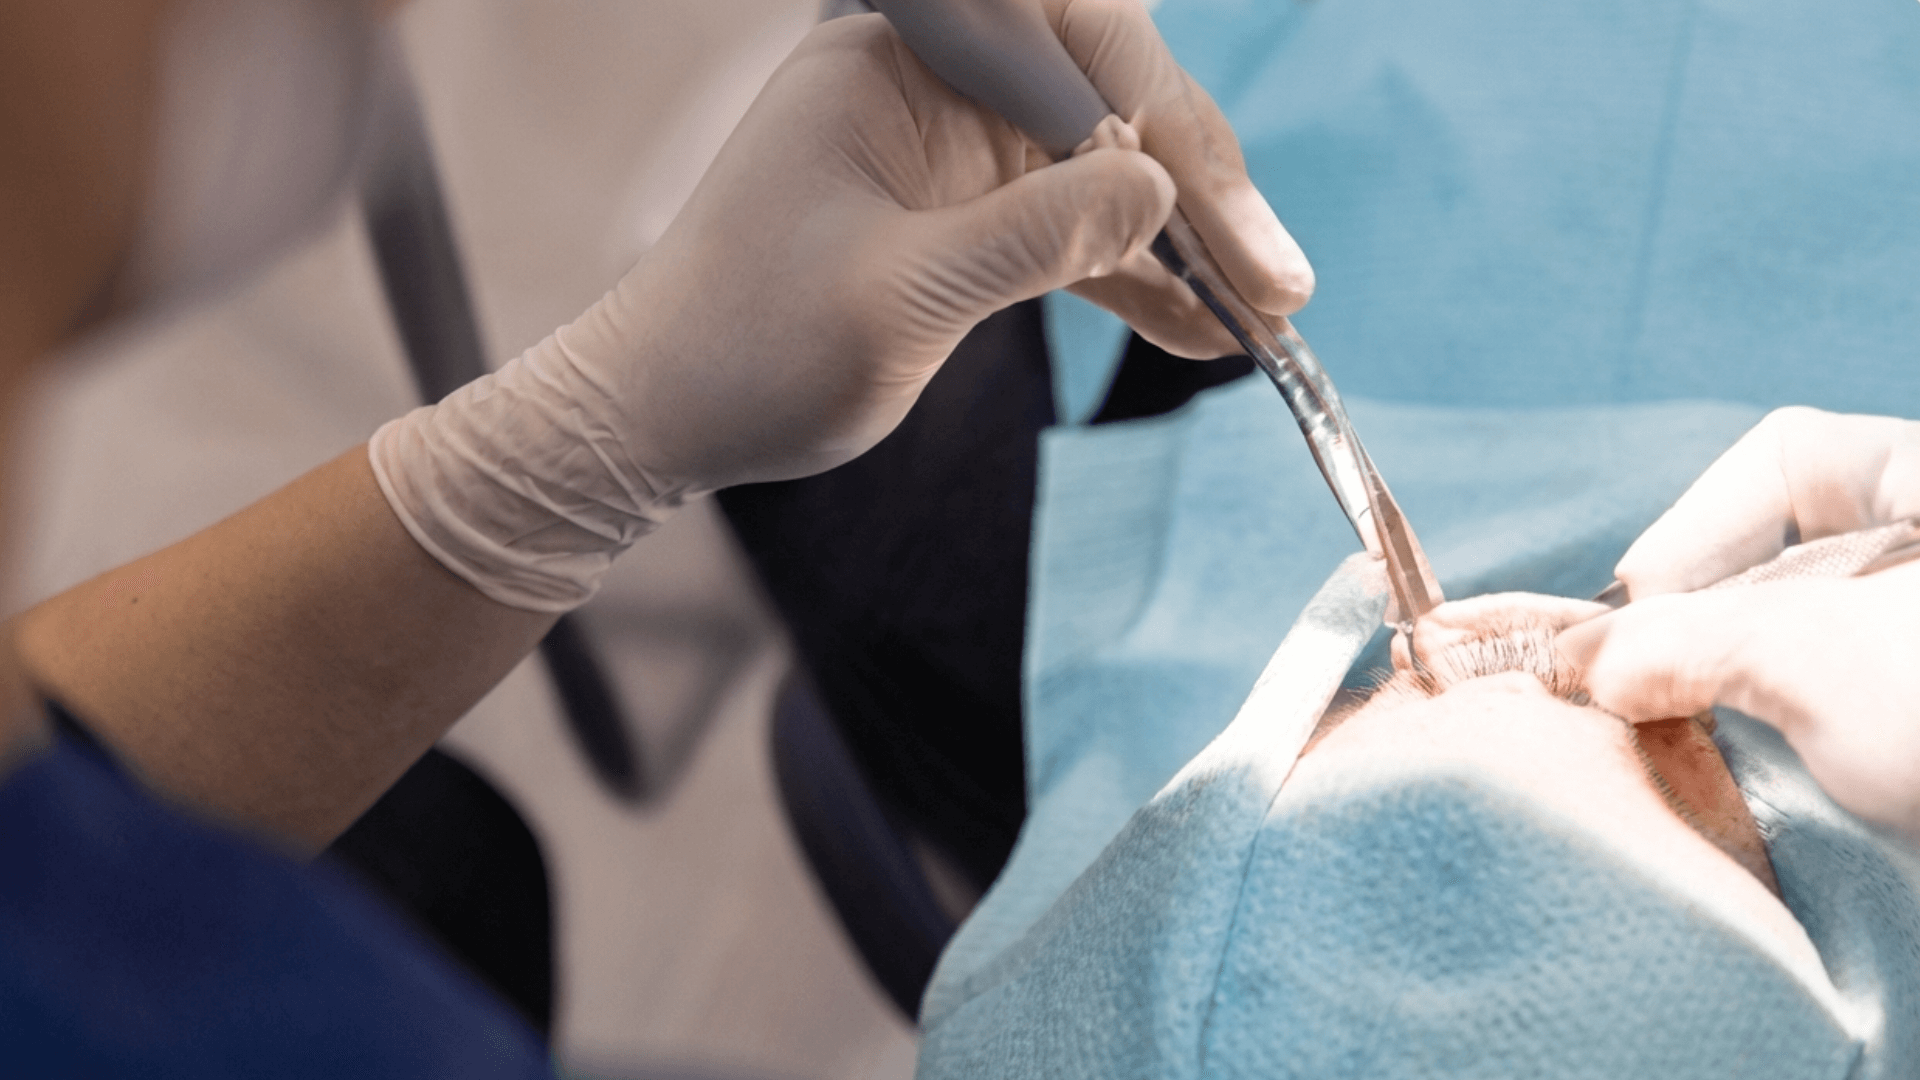

一次手術(インプラント埋入)

局所麻酔下で顎の骨にインプラント体を埋め込みます。

2つの視点で全方位の安全を確保

メインのオペ担当ドクターに加え、アシストも経験豊富なドクターが行います。2人のドクターが手術に関わることで、あらゆる視点から確実性と安全性を確保し、患者様への負担軽減や安心感も向上します。

2つの視点で全方位の安全を確保

メインのオペ担当ドクターに加え、アシストも経験豊富なドクターが行います。2人のドクターが手術に関わることで、あらゆる視点から確実性と安全性を確保し、患者様への負担軽減や安心感も向上します。